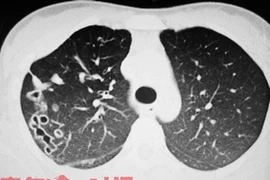

Bé 12 tháng tuổi viêm phổi vì rửa mũi nhầm bằng cồn 90 độ ảnh 1Bác sỹ điều trị cho bệnh nhân nhi tại Bệnh viện Bạch Mai. (Ảnh minh họa: TTXVN/Vietnam+)

Kết quả thăm khám lâm sàng cho thấy: trẻ tỉnh, không sốt, chảy nước mũi và ho nhiều. Mũi 2 bên của bé đỏ, thở khò khè… Các bác sỹ đã chỉ định làm các xét nghiệm và chụp tim phổi… Kết quả cho thấy, bé đã bị viêm phổi.